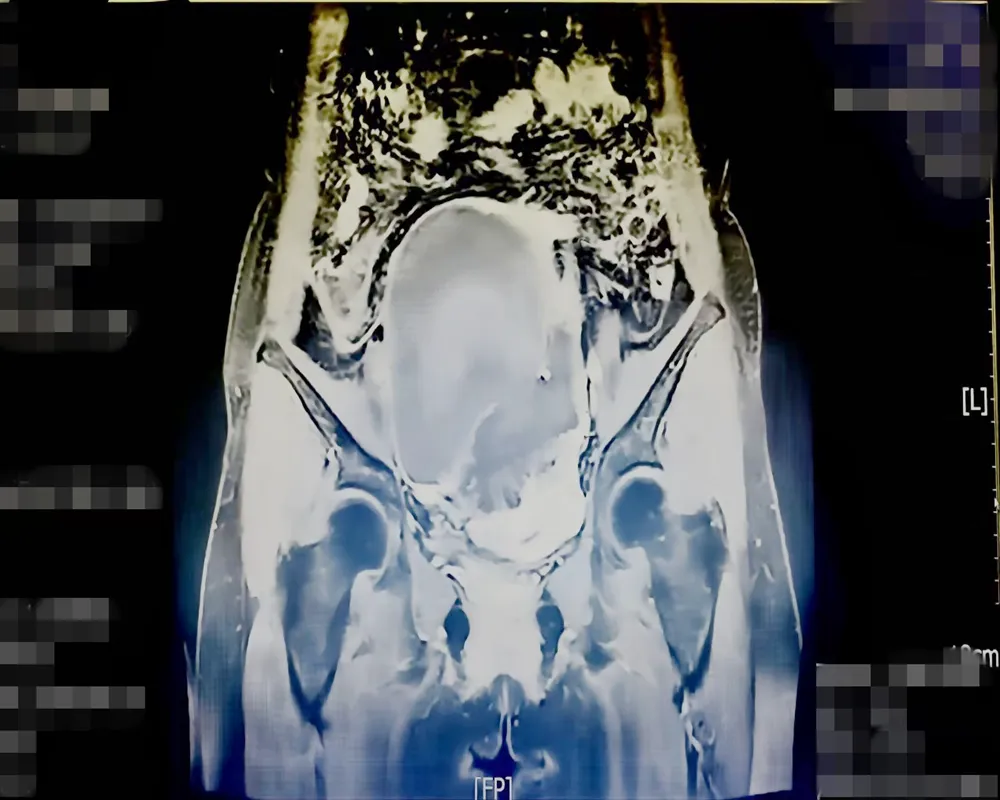

▲患者影像资料